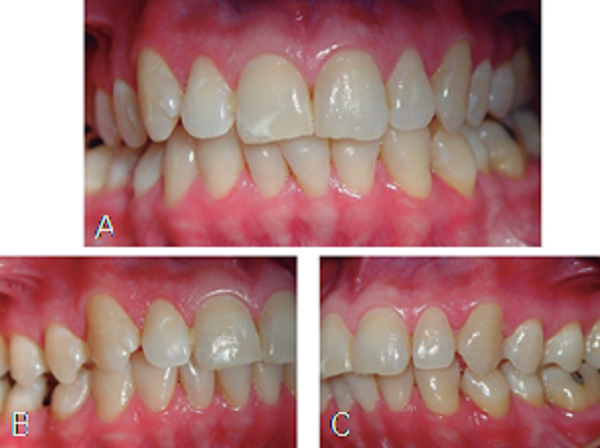

Al mes de iniciado el tratamiento era evidente la mejoría en piel, ya no tenía dolor y poco a poco las lesiones fueron disminuyendo de tamaño hasta prácticamente estar ausentes; intraoralmente los tejidos se ven muy bien, no había lesiones activas sólo algunas áreas blancas en margen gingival (Figura 5). En la actualidad, el paciente está libre de lesiones y la dosis de esteroides se redujo gradualmente hasta suspenderlos.

Sin embargo, el paciente no se ha adherido a un adecuado intervalo de mantenimiento periodontal y presenta un pobre control de placa bacteriana, lo cual es vital para la estabilidad y control en el largo plazo de este tipo de enfermedades.